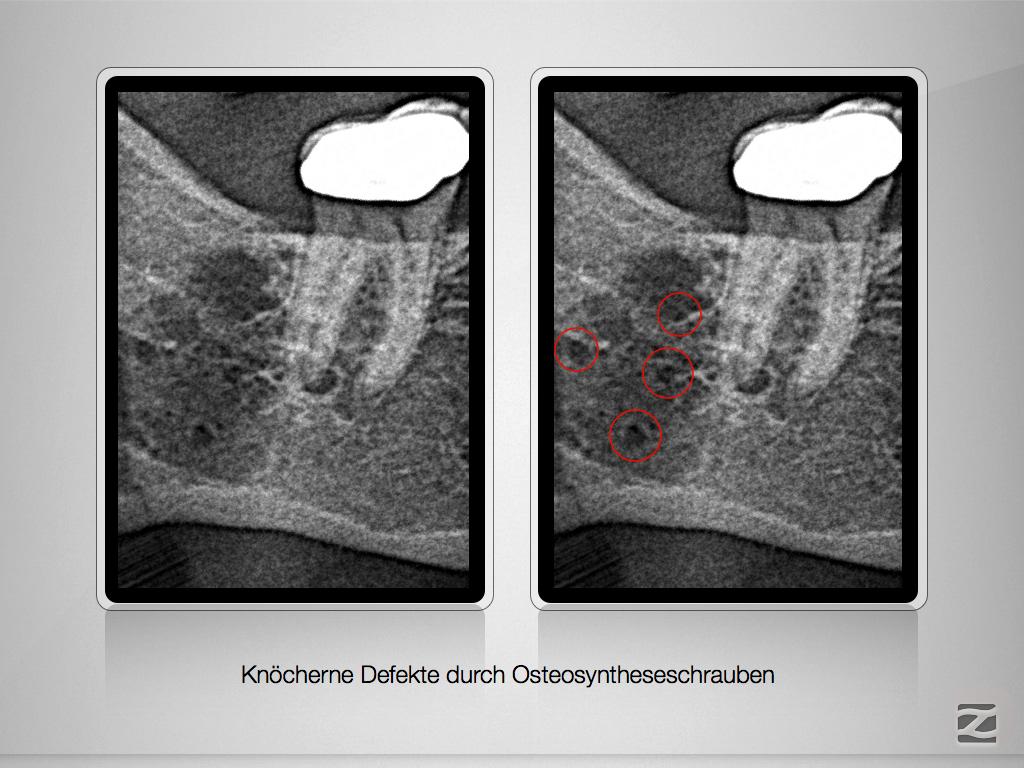

Apikale Aufhellung